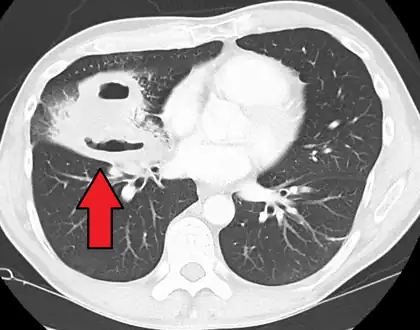

Pulmonary abscess on CT scan

Lung abscesses are often on one side and single involving posterior segments of the upper lobes and the apical segments of the lower lobes as these areas are gravity dependent when lying down. Presence of air-fluid levels implies rupture into the bronchial tree or rarely growth of gas forming organism.

a,b)Hollow lesion in the lower left lung field was diagnosed as a lung abscess